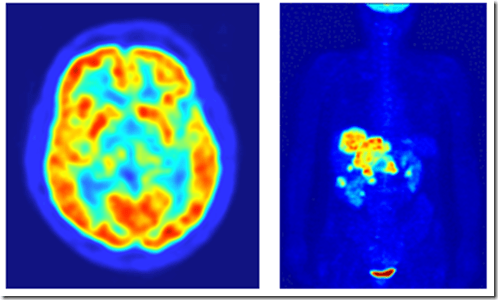

Positron emission tomography (PET) uses Fluorine-18, half-life of ~110 min

image

Right: normal metabolic function in the brain

Fluorodeoxyglucose or FDG carries the F18 to areas of high metabolic activity

90% of PET scans are in clinical oncology